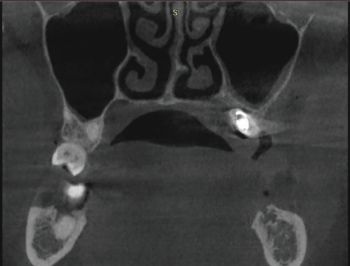

X-rays exams (i.e. OPG and CBCT) revealed the position of the displaced implant, which subsequently migrated near the ostiomeatal complex (OMC). It’s worth pointing out that immediately after their displacement, dental implants are usually located on the floor of the maxillary sinus or in the immediate vicinity; after a while, the displaced implants start to migrate against the gravitational force in the direction of the maxillary sinus ostium (as reported in the present clinical case) thanks to the strong mucociliary clearance by the sinus mucosa as well as nasal and intrasinus pressure changes. Notably, no reactive changes of the sinus membrane were observed (Figs. 1–5).

Fig. 2: Pre-op CBCT radiographic exam (coronal section)